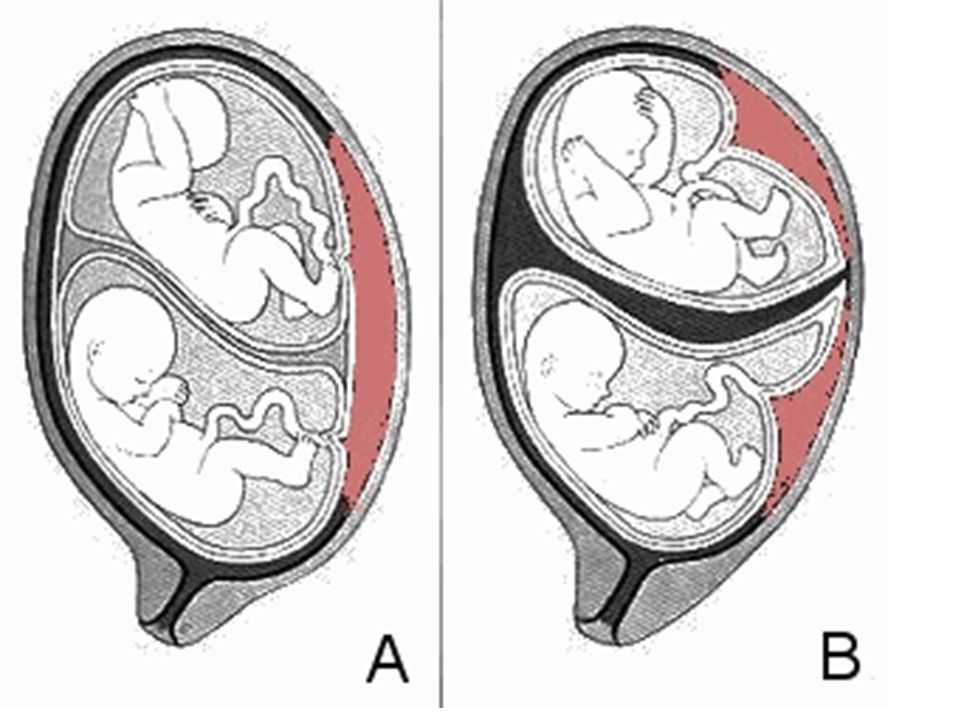

Околоплодный пузырь и плацента: структура и функции